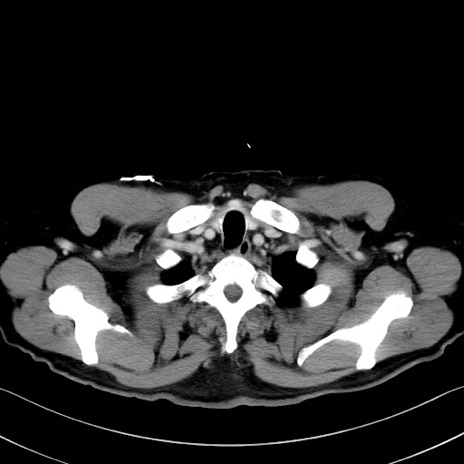

冠状断像